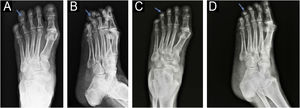

Na radiografia, era evidente erosão óssea associada a espessamento de tecidos moles na falange distal do quarto pododáctilo esquerdo (fig. 2). Uma biopsia excisional sem margens foi realizada para histopatologia.

Radiografias anteroposteriores (A) e laterais (B) do pé esquerdo antes da cirurgia: aumento da densidade do tecido mole e erosão óssea da falange distal (seta azul), lembrando aspecto de “taça” (B). Radiografias anteroposteriores (C) e laterais (D) do pé esquerdo dois meses após a cirurgia: recuperação parcial da estrutura óssea.